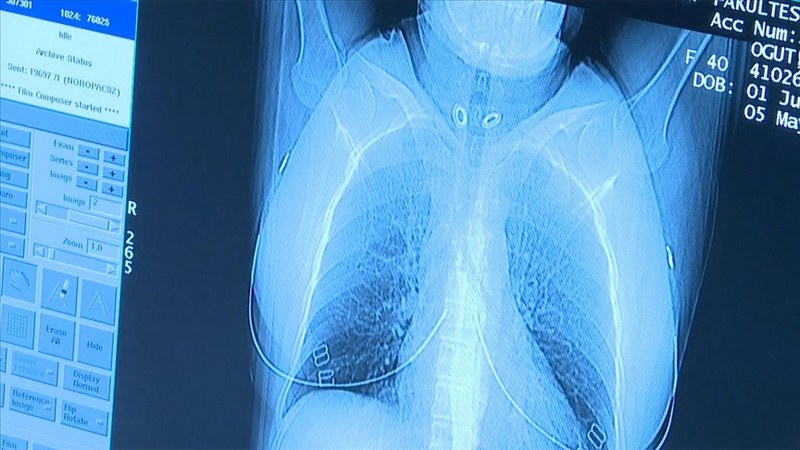

Vücudun iç yapı görüntülerini yorumlayan radyolojinin, tıbbın tüm branşlarında tanı ve tedavinin yanı sıra erken teşhisi sağlamada başarılı şekilde kullanıldığına işaret eden Tunçbilek, kanseri erken dönemde saptamada tarama programlarının büyük önem taşıdığını vurguladı.

“Akciğer kanserinde erken tanı ve doğru evreleme ile radyolojik görüntüleme yöntemleri hasta yönetiminde önemli rol oynamaktadır. Akciğer kanserinde erken teşhis yüzde 77 oranında hayat kurtarmaktadır. 50 yaş üzeri ve 20 yıl ve daha uzun süreli sigara içen kişilerde yıllık düşük doz akciğer tomografisi çekilmesi önerilmektedir. Bu sayede, erken dönemde kanser tespiti yapılabilmekte ve tedavisi planlanabilmektedir. Ancak öncelikle kişinin yüksek risk grubunda olup olmadığı hekimi tarafından belirlenmeli ve gerek duyulduğu takdirde tarama yapılmalıdır.

İleri evre akciğer kanserinde tam tedavi oranı büyük oranda mümkün değilken, erken dönemde teşhis ve tedaviyle başarılı sonuçlar alınabilmektedir. Bu nedenle, risk grubundaki kişiler için belirlenen sürelerde düşük doz akciğer tomografisi hayati önem taşımaktadır.”